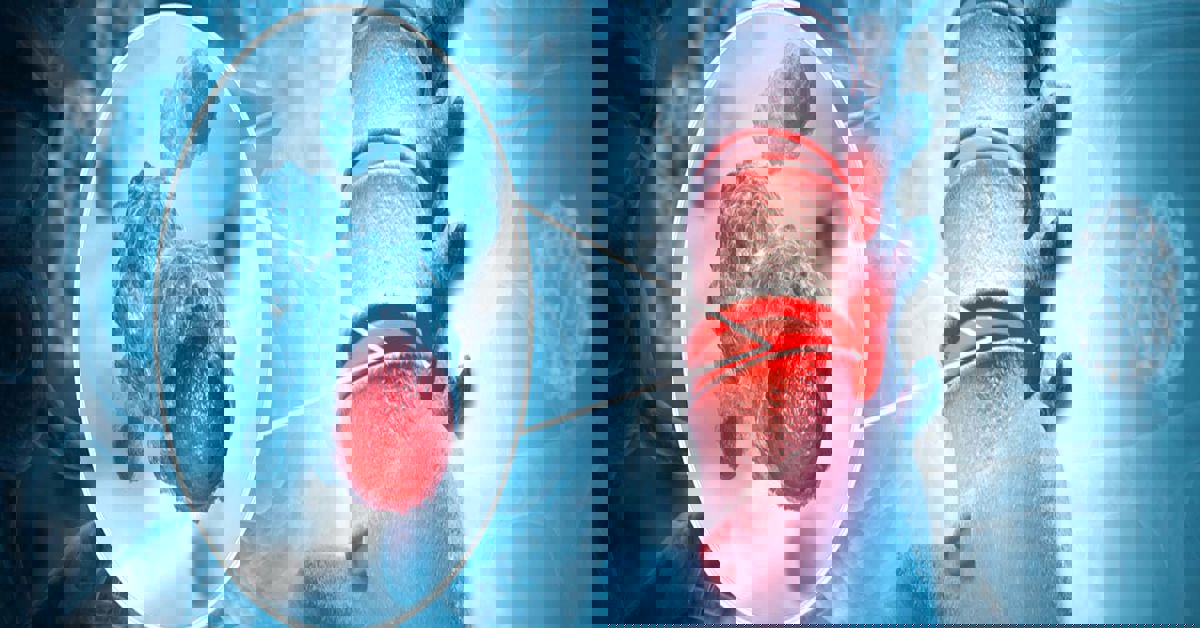

Kemik tümörleri, kemik dokusunda kontrolsüz hücre büyümesiyle ortaya çıkan ve her yaş grubunu etkileyebilen yapılardır. Bu tümörler iyi huylu olabileceği gibi kötü huylu da olabilir. Her iki durumda da erken tanı büyük önem taşır. Çünkü kemikte meydana gelen küçük bir değişiklik bile zaman içinde ağrıya, hareket kısıtlılığına ve kırık riskine yol açabilir.

Tedavi, genellikle tümörün büyüme hızının arttığı veya hastada belirgin şikâyetlerin ortaya çıktığı durumlarda gündeme gelir. Ağrı, şişlik, kemikte şekil bozukluğu ya da açıklanamayan hareket kısıtlılığı gibi bulgular önemli uyarılardır. Bu aşamada görüntüleme yöntemleriyle tümörün yeri ve boyutu değerlendirilir. Ortaya çıkan tabloya göre kemik tümörü tedavisi uygulanıp uygulanmayacağına karar verilir.

Kemik tümörleri, kemik dokusunda oluşan iyi huylu veya kötü huylu kitlelerdir. Belirti vermeden ilerleyebilir ve bazen sadece rutin görüntülemelerde tespit edilir. Bu nedenle erken tanı tedavi başarısında kritik bir rol oynar. Tedavi yönteminin seçimi tümörün yapısına, büyüklüğüne, hastanın yaşına ve genel sağlık durumuna göre belirlenir.